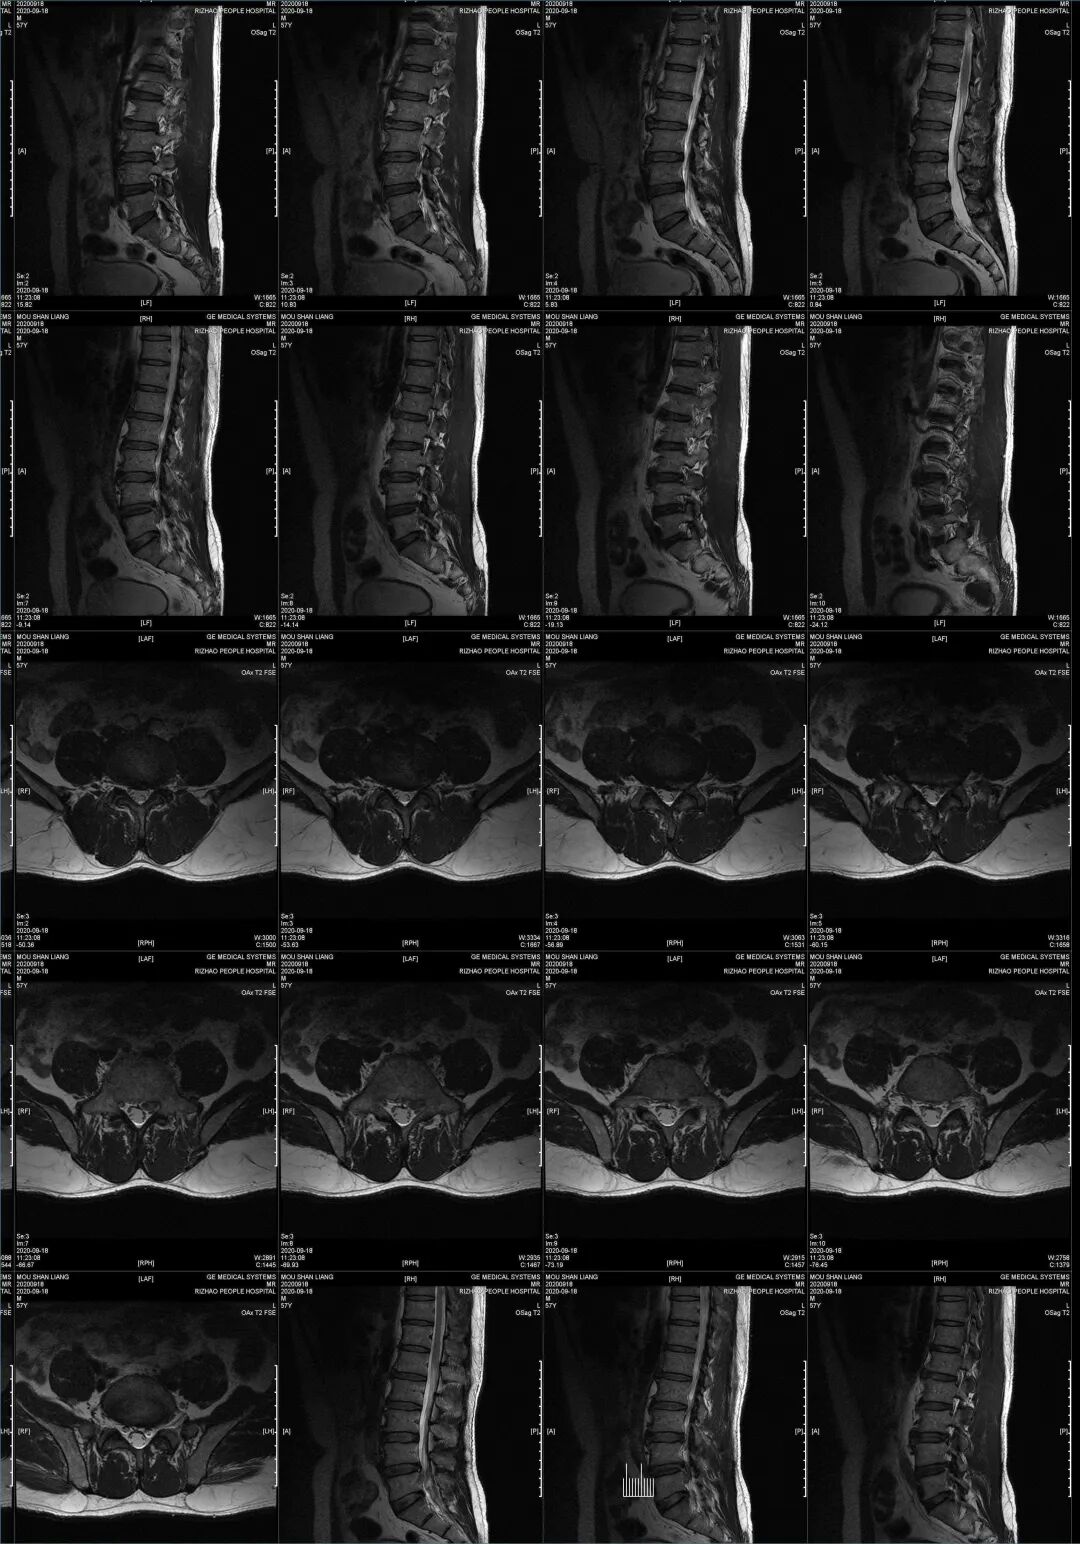

影像学检查:腰椎MRI:

1、L4-5、L5-S1椎间盘突出

2、L2-3、L3-4椎间盘膨出

3、L5椎体后等信号,椎间盘组织脱垂可能

4、腰椎骨质增生

5、腰部皮下软组织局部轻度水肿

图2:术前影像

图3:术前影像